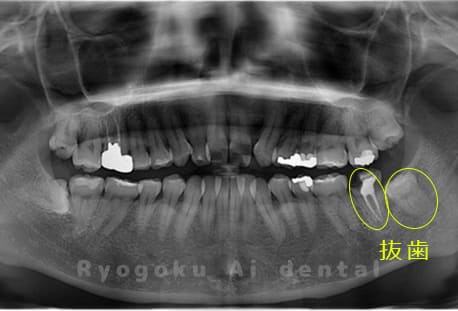

他院で右下の根の治療を行い、セラミックを被せる説明をされていたが、根の治療が終わらないため転院された患者さんです。隣の親知らずの抜歯の必要性と、根の治療を行なっている歯牙の予後が悪いため、移植治療を提案し、右下の親知らずの抜歯と同時に、右下の奥歯(7番)への移植治療を行いました。被せ物を行う必要もなく、順調に経過してます。